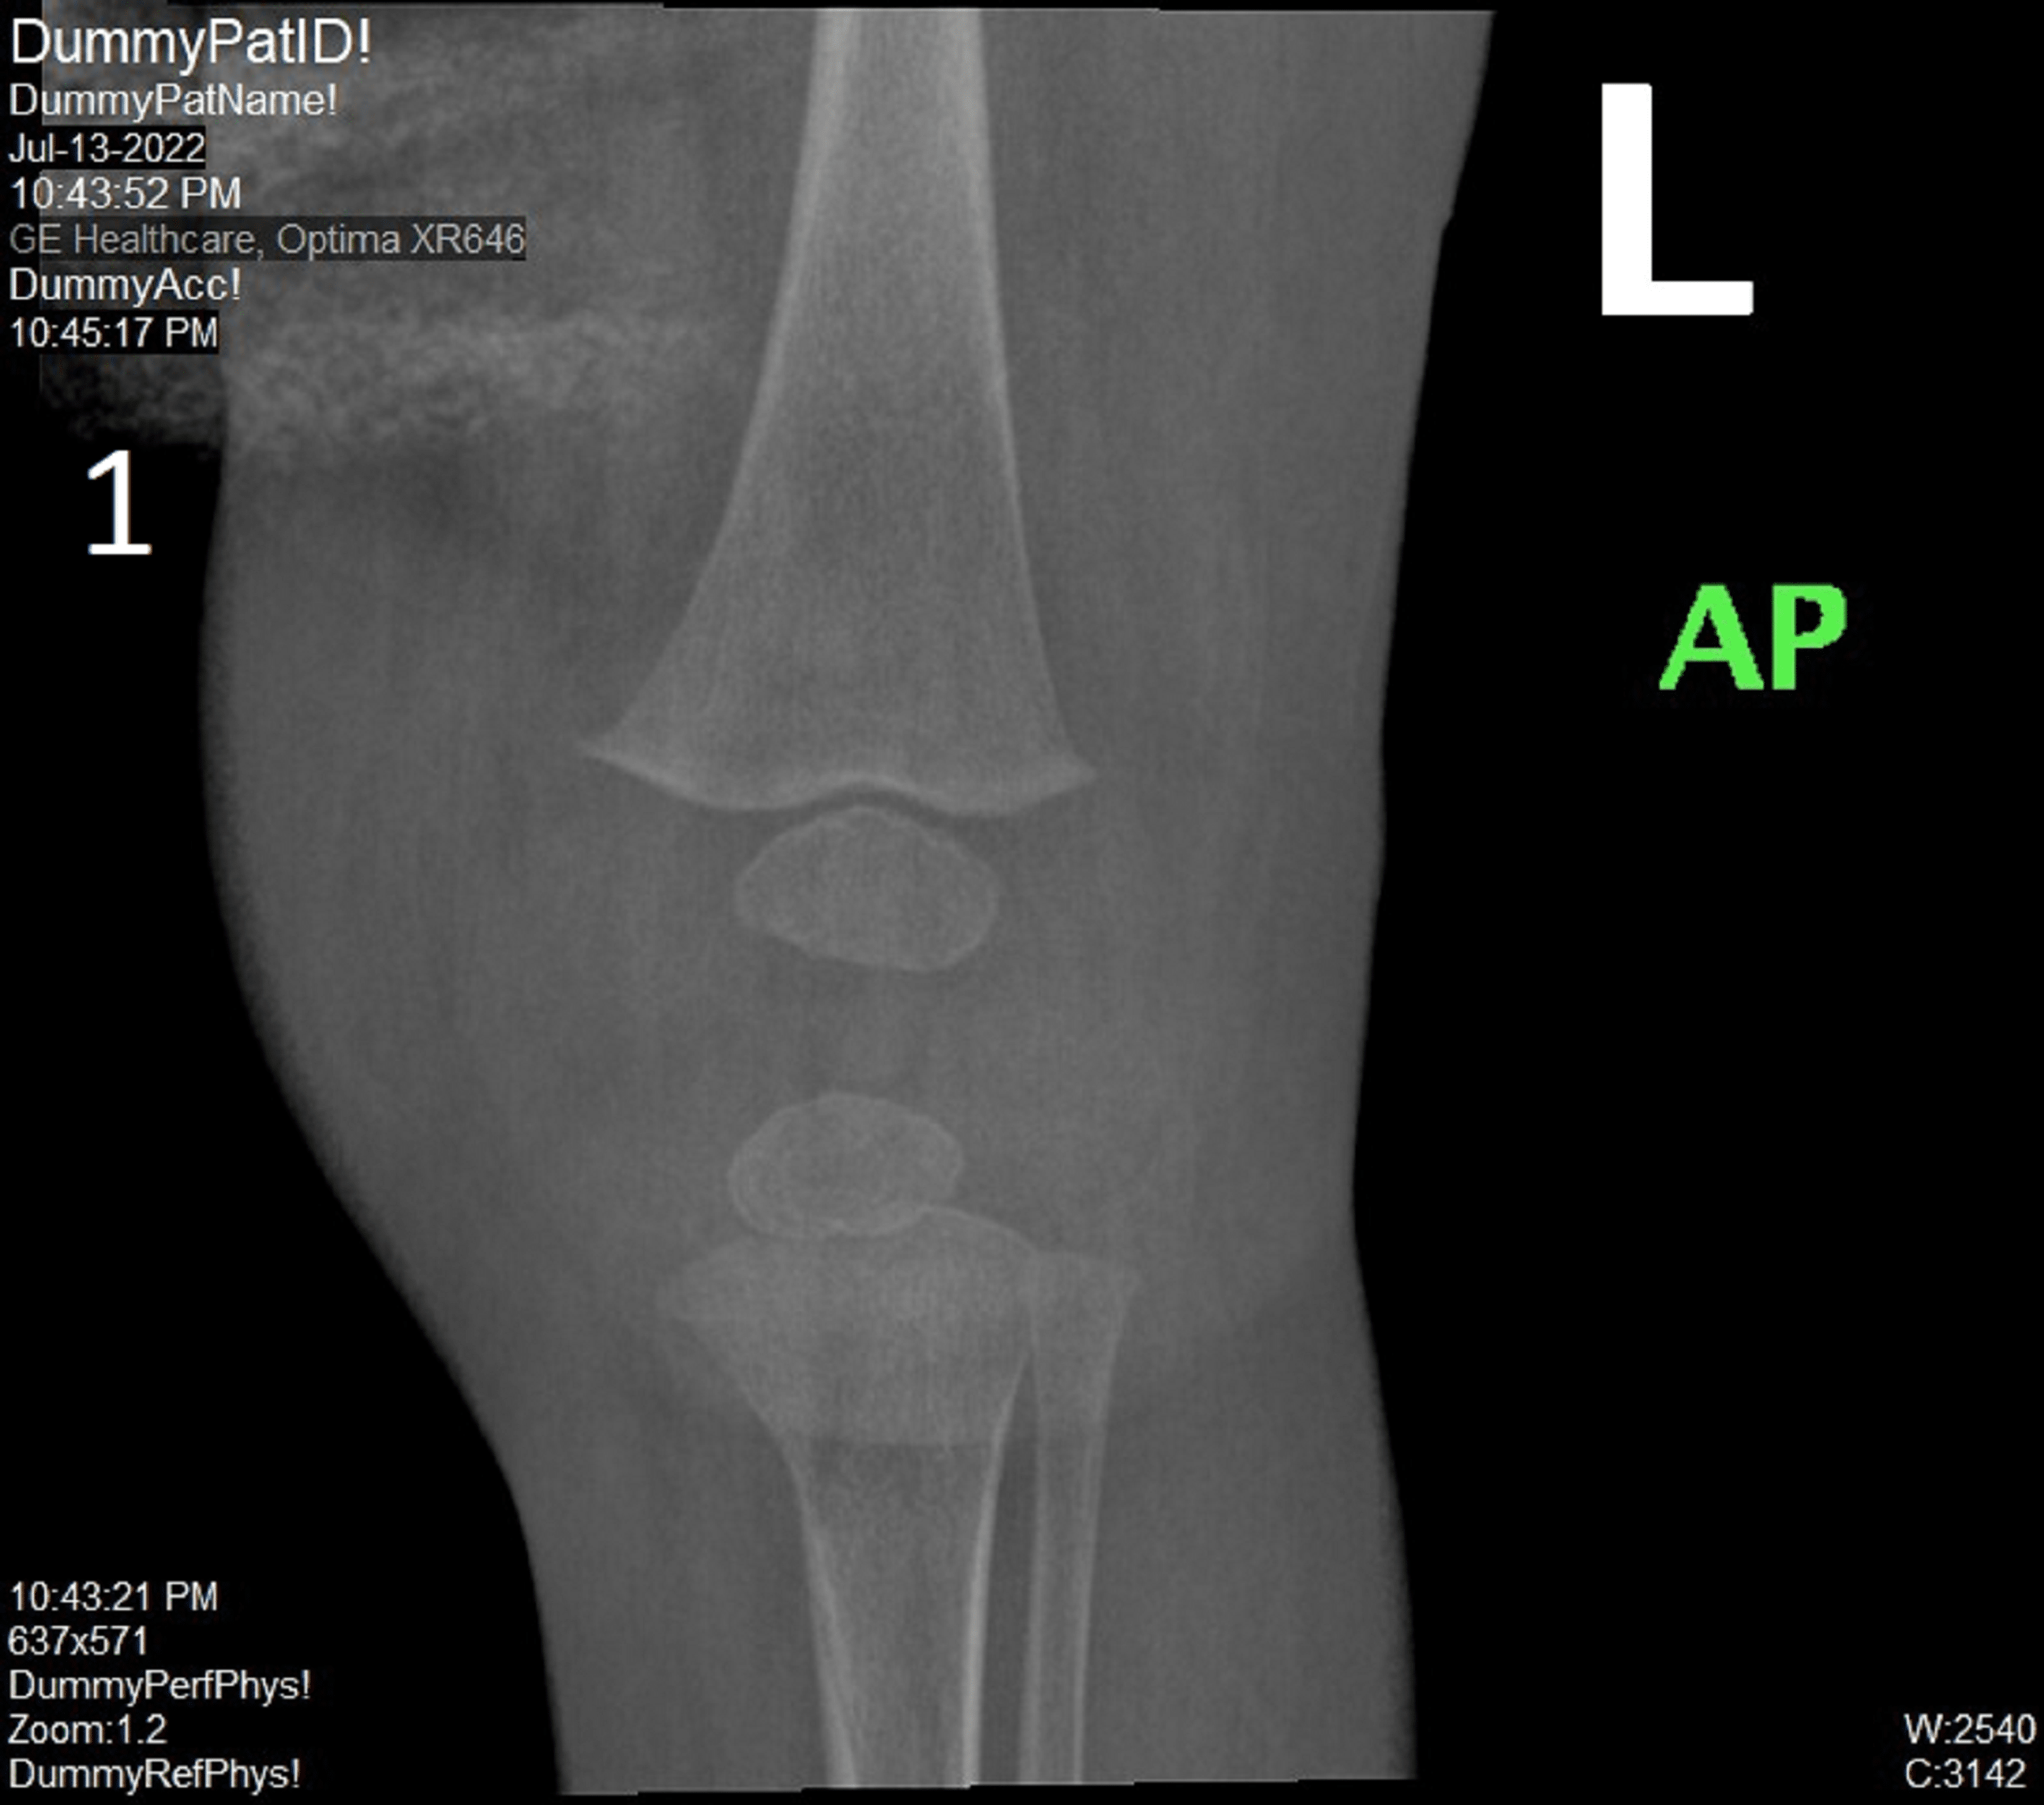

(PDF) Left knee septic monoarthritis in a pediatric patient due to Septic Arthritis Pediatrics In Review Therefore, the aim of this systematic review is to provide a comprehensive analysis of the diagnosis, management, and. Assess the laboratory and imaging tests that can be utilized to facilitate the. Septic arthritis affects children of all ages; Pediatric septic arthritis can be accompanied. Acute septic arthritis in children is usually hematogenous. We investigated the pathogenic, clinical, and laboratory characteristics. Septic Arthritis Pediatrics In Review.

(PDF) Left Knee Septic Monoarthritis in a Pediatric Patient due to Septic Arthritis Pediatrics In Review It is more common in boys, and it most often affects the large joints of the lower limb. Describe the signs and symptoms of pediatric septic arthritis. We investigated the pathogenic, clinical, and laboratory characteristics of children diagnosed with septic arthritis (sa) during the. Pediatric septic arthritis can be accompanied. Therefore, the aim of this systematic review is to provide. Septic Arthritis Pediatrics In Review.